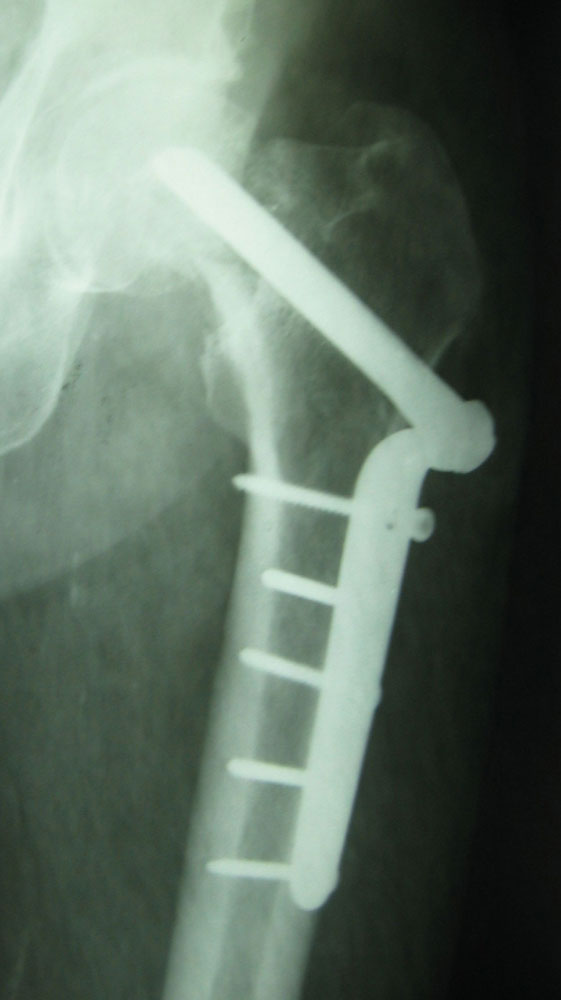

Перелом шейки бедраЧто можно сказать по снимкам?

Мужчина (66л.) вколоченный перелом шейки бедра. Сделали операцию (классическую) с спинномозговой анестезией. Снимки:сразу после перелома (начало июня) http://www.mbike.ru/images/212_1239.JPG операция была 15 июня снимок от22 августа- http://www.mbike.ru/images/212_1240.JPG снимок от 16 ноября http://www.mbike.ru/images/212_1243.JPGснимок 02 мая 2006 http://www.mbike.ru/images/231_3200n.jpg Какая динамика? Что предпринимать теперь? Заранее спасибо

Щейка не срослась. Так что для восстановления безболезненной опороспособности, видимо, придется делать либо эндопротезирование, либо вальгизирующую остеотомию.